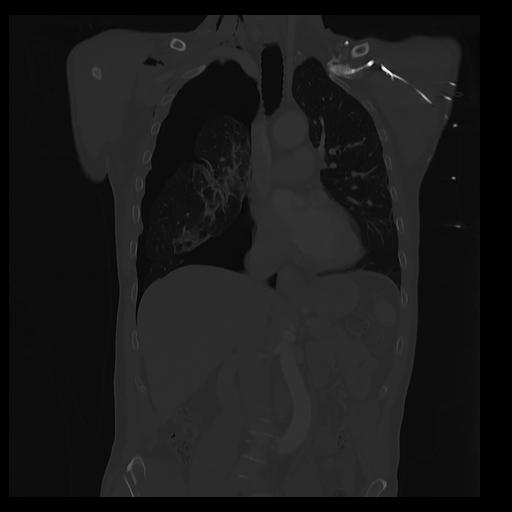

32 PULMON,CE,Coronal,3.000,PULMON,Coronal,